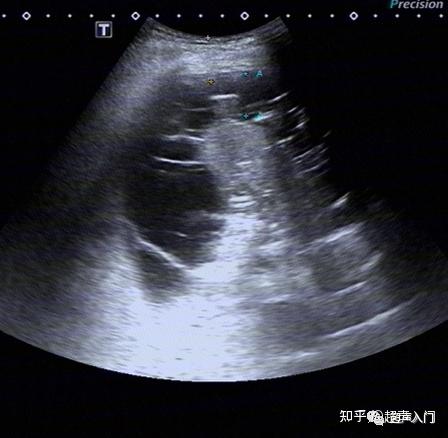

胸腔积液的超声诊断,既简单又复杂

图片尺寸448x438